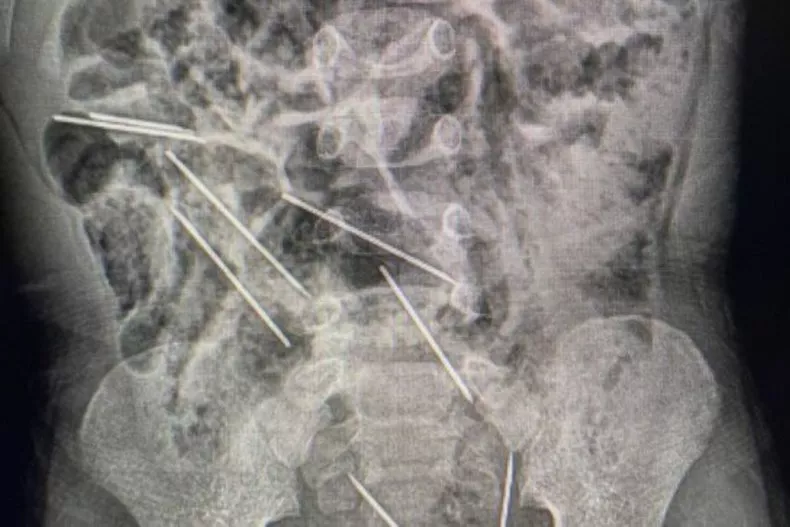

Οι γιατροί επαρχιακού νοσοκομείου στο βόρειο Περού, ξαφνιάστηκαν όταν είδαν την ακτινογραφία του λιλιπούτειου ασθενή που έφθασε στα επείγοντα από αγρόκτημα της περιοχής Ταρατόπο 622 χμ από την πρωτεύουσα Λίμα. Στο κορμί του δίχρονου παιδιού εντοπίστηκαν όχι μία και δύο, αλλά 8 μεγάλες βελόνες από αυτές που χρησιμοποιούνται για ενέσεις σε αγελάδες.

Δύο ώρες διήρκεσε η περίπλοκη και λεπτή επέμβαση για την αφαίρεσή τους. «Μόλις ανοίξαμε την κοιλιά διαπιστώσαμε ότι αυτά τα μεταλλικά σώματα ήταν βελόνες Νο. 21 για ενέσεις, κομμένες στην άκρη. Βρήκαμε δύο στη δεξιά πλευρά του… Πηγή